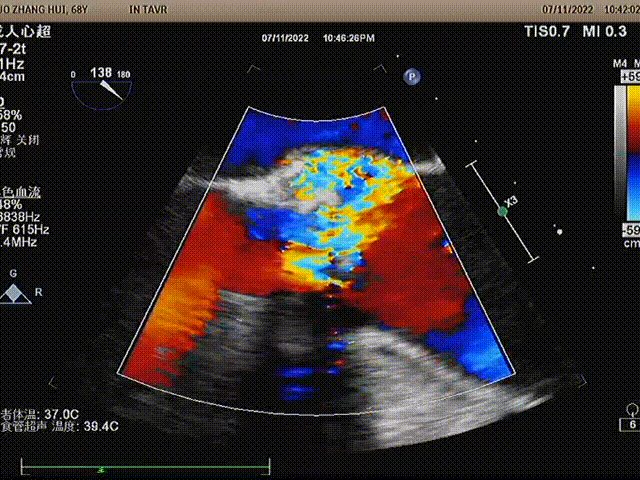

CDFI:主动脉瓣前向血流速度加快Vmax4.8m/s,PGmax93mmHg,PGmean56mmHg,瓣下探及少量返流;二尖瓣前向血流频谱A>E;e=5cm/s,a=9cm/s,E/e=26;二尖瓣上探及少量返流;余瓣膜口两侧未探及异常血流信号。心内及大血管水平未见分流。

球囊扩张后,瓣膜形态完美,超声复查无瓣周漏,冠脉开口无堵塞